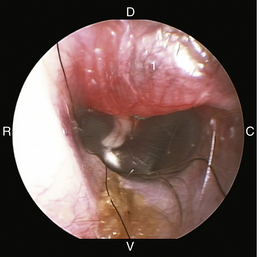

image

Figure 20-8 Normal canine tympanic membrane of the left ear. 1, Pars flaccida; 2, pars tensa; 3, stria mallearis; 4, bulla septum; C, caudal; D, dorsal; R, rostral; V, ventral.

(Courtesy of Dr. Lynette Cole, The Ohio State University, Columbus, Ohio.)